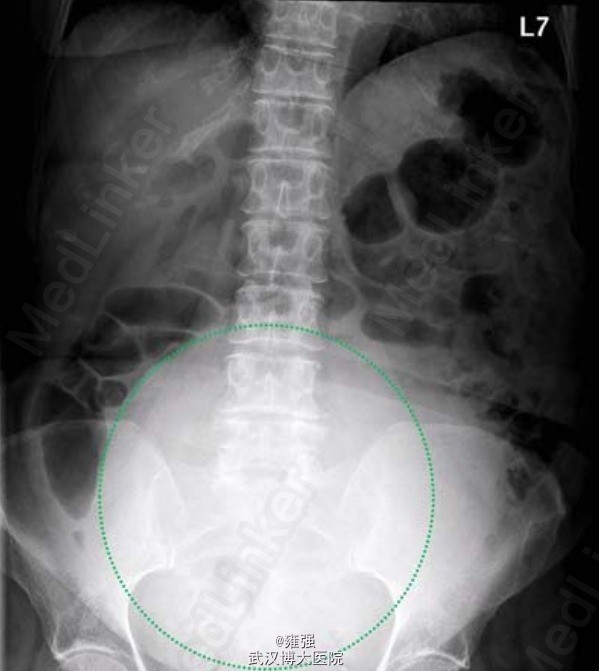

辅检:肿瘤标记物(CEA、CA19-9、CA125)均在正常范围,入院后腹部X片示下腹部出现增强的不透光区(如下图示)。术前TAP分段CT示盆腔内大型、界限清楚、中线测量为 18.8 cm×13.3 cm×18.2 cm、混合衰减的包块(如下图示),位于子宫前、膀胱之上,独立于子宫存在,考虑为起源于卵巢。